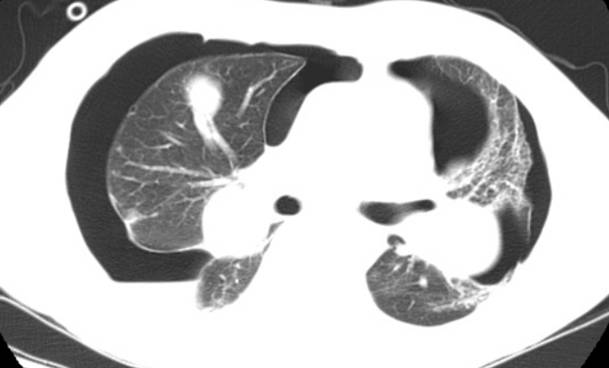

2.空洞或空泡样肺转移瘤:

原发灶多见于消化及呼吸系统,以鳞癌、腺癌、黑色素瘤、肉瘤、胚胎细胞瘤和移行细胞瘤多见,约占4%。转移性空洞形成机制可能与鳞癌中心角化物排空、腺癌黏液退变后黏液排空、肿瘤血供不足引起坏死、放化疗、肿瘤向支气管内侵犯形成活瓣等机制有关。 医学百科网 | YxBaike.Com

CT影像常多发,多为圆形,壁薄,光滑均匀,也可以表现为厚薄不一,肺门侧的壁较厚,外侧的壁薄,也可出现厚壁空洞,空洞壁常有明显强化。空洞性病变倾向于分布在胸膜下或叶间裂下,越靠近胸膜,空洞越小,直径较大的空洞多分布在肺的中带。厚壁空洞病变可随着病灶增大而出现分叶、毛刺及壁结节等恶性空洞的特点。

空洞性肺转移瘤变化快,短期内可见肿瘤增大、增多,有时可在治疗后自行消失。有学者认为空洞壁厚1-2mm及以下者不太符合缺血坏死所形成空洞的形态,因而称空泡更合适。空泡样转移瘤的瘤壁菲薄光滑,质均匀,可与肺纹理相连。

肺腺癌肺转移 医学百科网 | YxBaike.Com

牙龈癌肺转移

左侧背部的平滑肌肉瘤肺转移 医学百科网 | YxBaike.Com

食管鳞癌肺转移 医学百科网 | YxBaike.Com